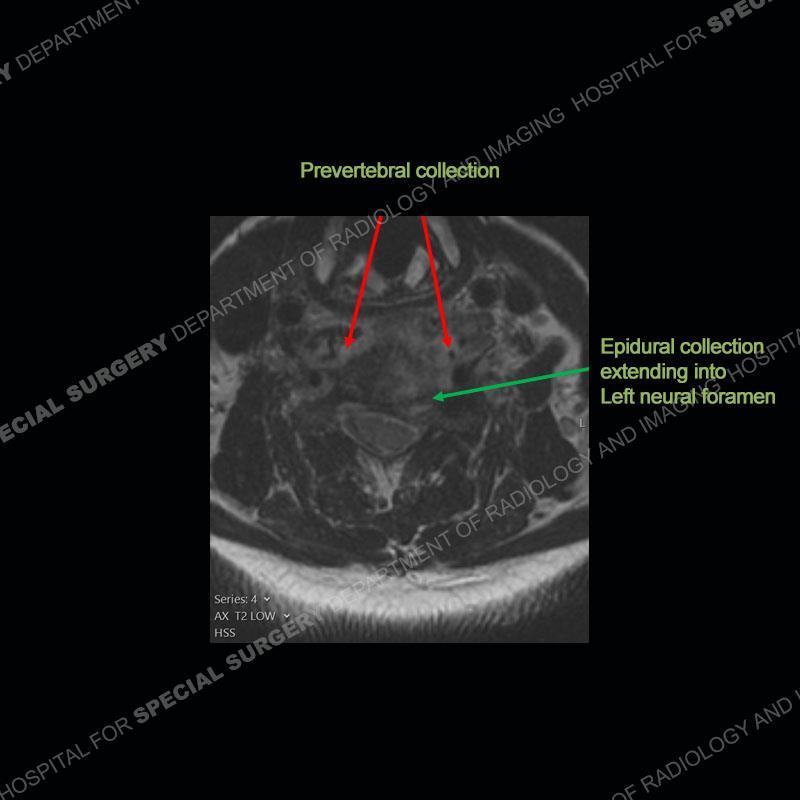

The radiographs demonstrate a prevertebral soft tissue fullness centered at C5-C6 that persists even on extension. There is a slight loss of disc height at C5-C6. The CT more readily shows the prevertebral soft tissue swelling at C5C6 where there is a punctate focus of gas. On the MRI, there is a marked amount of edema and a heterogeneous collection in the prevertebral soft tissue at C5-C6. Edema is present of the C5 and C6 vertebral bodies with a loss of the normal architecture about the disc space. A heterogeneous epidural collection has formed that causes compression of the spinal cord asymmetric to the left side and also precipitates severe left sided neural foraminal stenosis.